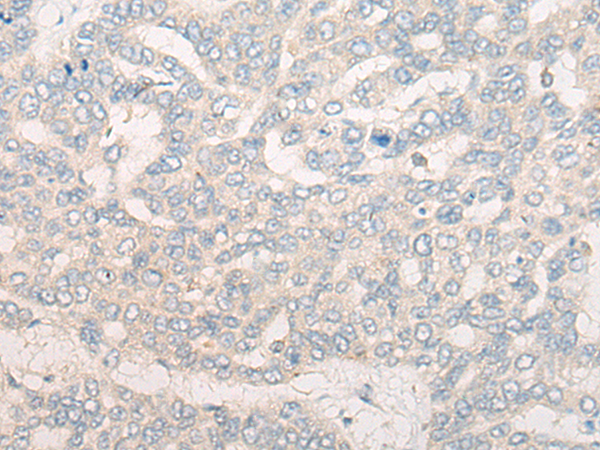

分类: 科研抗体货号: P13262别名: DMN; SYN应用: IHC反应种属: Human